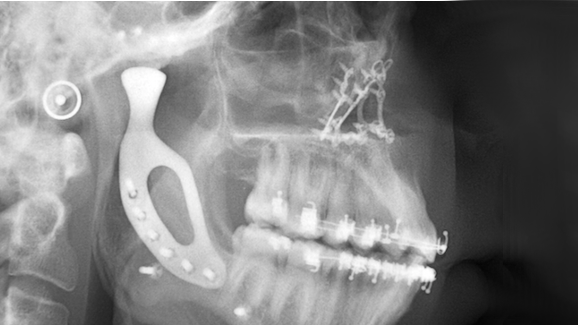

MELBOURNE, Australia: In collaboration with medical engineers, oral and maxillofacial surgeons at the University of Melbourne have recently implanted a temporomandibular joint prosthesis in a young man suffering from a rare congenital jaw deformity. This is the first time a custom-made mandibular joint replacement using 3-D printing technology has been performed in Australia.

The patient, Richard Stratton, was born with condylar aplasia, a developmental defect of the mandibular condyle. He was missing a temporomandibular joint, which resulted in a lack of growth in the left side of his face and a noticeably skew mandible. The condition also affected jaw motion, chewing capacity and facial expression.

Stratton’s jaw was surgically reconstructed with a new titanium prosthesis. It was manufactured using the latest 3-D metal printing technology, which was developed and tested in collaboration with 3D Medical, one of Australia’s leading medical and health care technology providers.

According to the university surgeons, the biomechanical and clinical results look promising. They believe that this technology will help facilitate the research and manufacture of customised high-tech implantable devices in Australia.